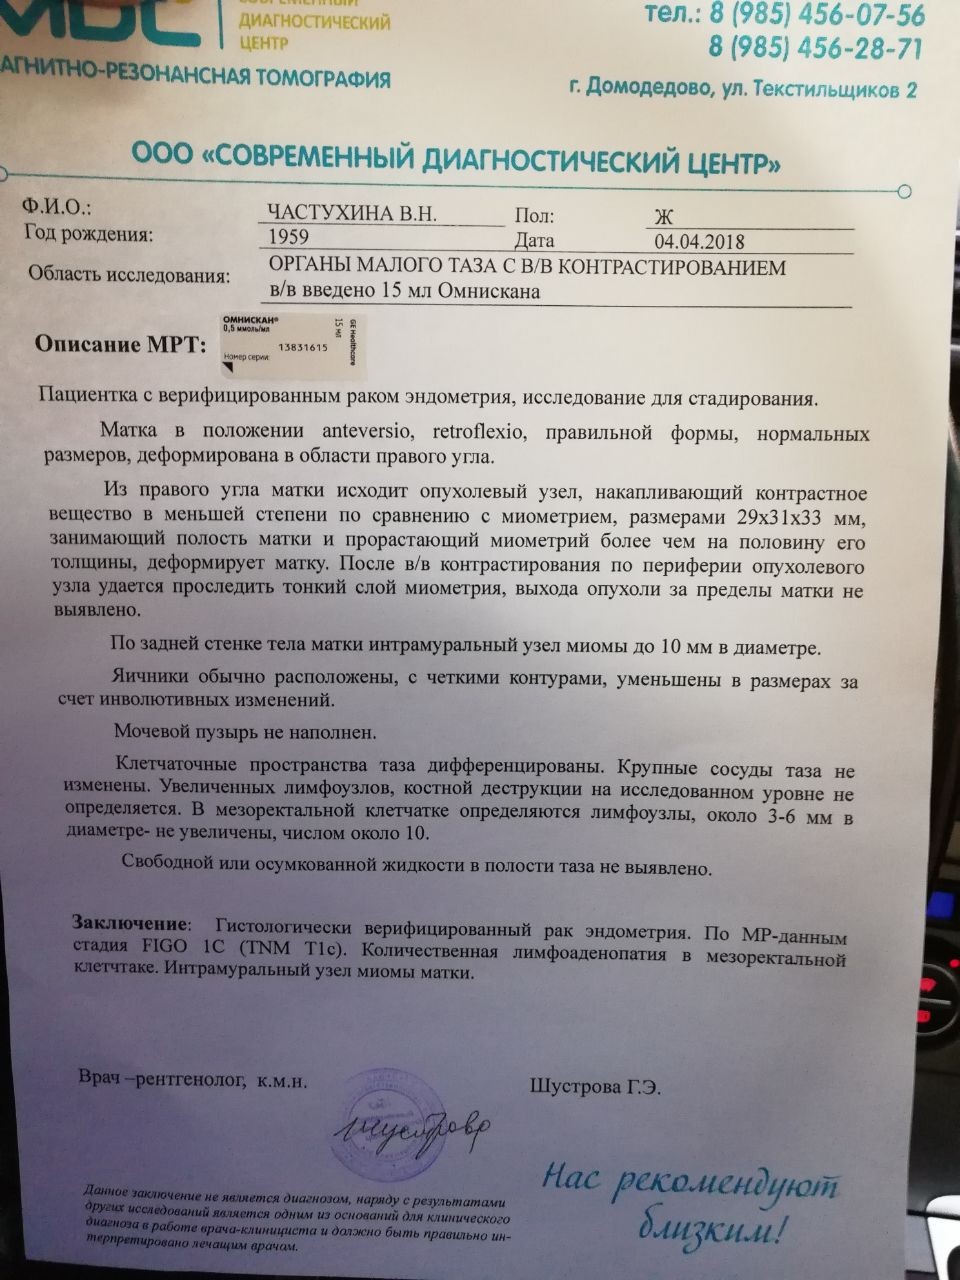

Злокачественная опухоль на матке заключение

Лейомиосаркома матки мрт

Примеры фото МРТ малого таза у женщин

Ниже представлены примеры фотографий МРТ малого таза у женщин, позволяющие увидеть, как выглядят снимки и какие изменения могут быть обнаружены специалистами.